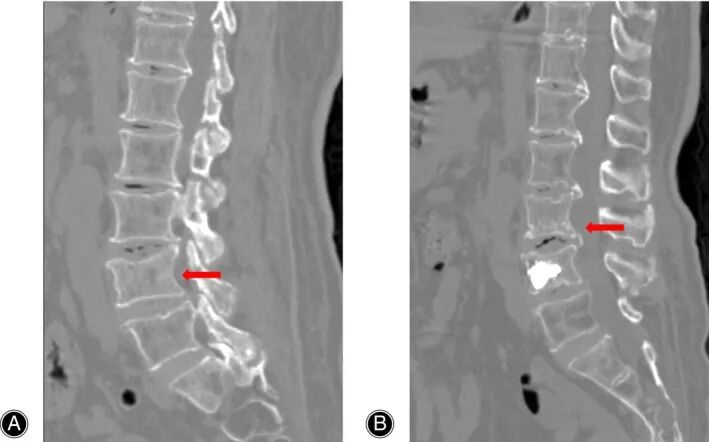

分割结果可视化

本文提出的后处理方法有效识别并剔除了因体素分类离散性产生的异常分割区域,从而提升了模型的整体分割精度。

一例71岁女性患者在术后被模型成功预测为高风险,并于一年后发生实际再骨折(L4→L3),有效验证了模型的前瞻性预警能力。